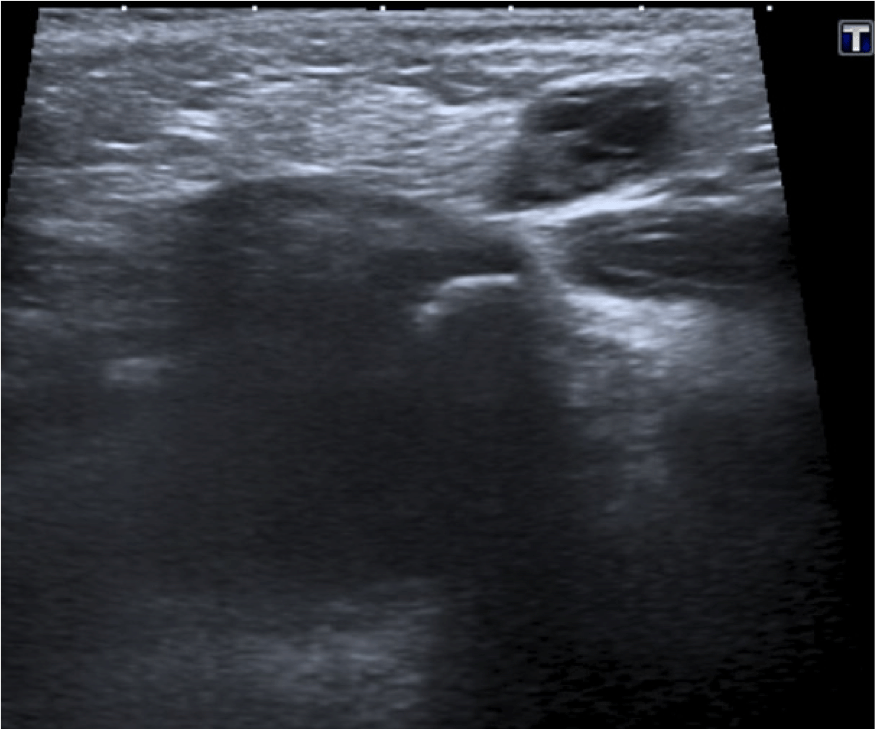

- La ecografía es la técnica de elección (ecógrafo de alta frecuencia)

- El ovario se identifica como una masa con quistes periféricos que representan los folículos.

Como ya comentamos, el diagnóstico precoz es importante para evitar que la hernia se complique. Si la torsión del ovario se produce, el compromiso primero venos y linfático y luego arterial produciran a los signos de inflamación , congestión y finalmente isquemia. Los pacientes pueden presentar clínica y signos de irritabilidad, dolor, vómitos, gangrena y necrosis tisular. La imágen ecográfica de torsión ovárica es la de un ovario agrandado con quístes, ecogenicidad heterogénea, sin captación de flujo Doppler color y repercusión de la grasa adyacente.

La morfología del ovario, como ya hemos descrito, es el de una masa que puede o no presentar en el momento del estudio estucturas quísticas periféricas que en la mujer adulta miden entre 15 y 20 mm. Otros autores usan los siguienes términos para referirse a ovarios con estructrucas quísticas: